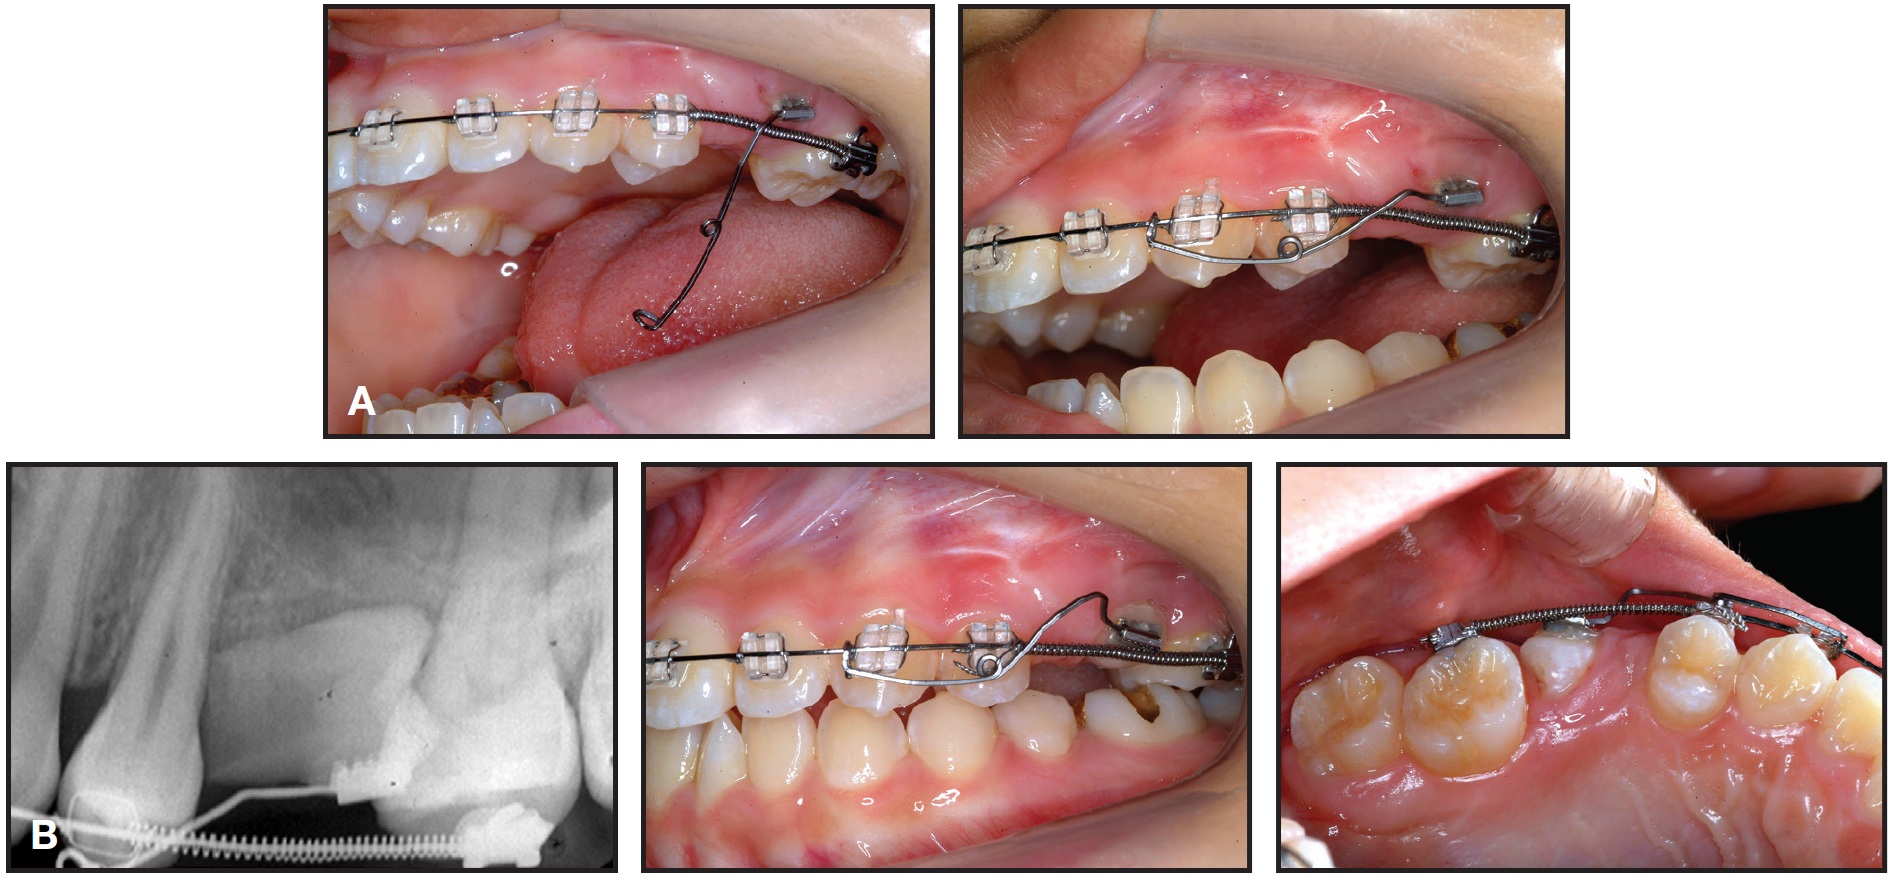

An .018" × .022" MBT-prescription Inspire ICE* clear fixed appliance was bonded in the upper arch. After three months of initial leveling on .014", .016", and .016" × .022" G4** nickel titanium archwires, an .016" × .022" stainless steel archwire was inserted. The patient was then referred for extraction of the retained tooth and exposure of the impacted premolar by an oral surgeon. A metal lingual button was bonded to the impacted tooth, and a twisted stainless steel ligature wire was tied to the attachment (Fig. 2). The ligature wire was drawn inferiorly through the sutured edges of the flap, so that the surgical site could be completely closed.

After seven days of healing, orthodontic treatment was resumed. Traction was applied to the twisted stainless steel ligature to bring about full eruption of the tooth. Since the distance between the ligature wire and the main archwire was too short to apply force, a stepdown bend was made in the archwire, and an open-coil spring was inserted between the first molar and first premolar to open and maintain adequate space for the second premolar (Fig. 3). The progress of impacted tooth movement was evaluated monthly (Fig. 4). After three months, to produce more clockwise rotation of the impacted tooth, the metal button was replaced by a minitube and an .016" × .022" TMA*** auxiliary wire was bent and attached (Fig. 5). Three months later, the wire was activated to create an additional rotational moment (Fig. 6).

Fig. 2 After three months of upper leveling and alignment, metal lingual button bonded to impacted upper left second premolar, and twisted stainless steel ligature wire tied to attachment.

Fig. 3 After one week of healing, stepdown bend made in main .016" × .022" stainless steel archwire to increase distance for eruption force application; open coil spring inserted between first molar and first premolar to open space for second premolar.

Fig. 4 Impacted premolar after one (A), two (B), and three (C) months of eruption.

Fig. 5 Minitube bonded to impacted premolar, and .016" × .022" TMA*** auxiliary wire bent and attached.

Fig. 6 A. Three months later, auxiliary wire activated to create additional rotational moment. B. After 11 months of treatment.